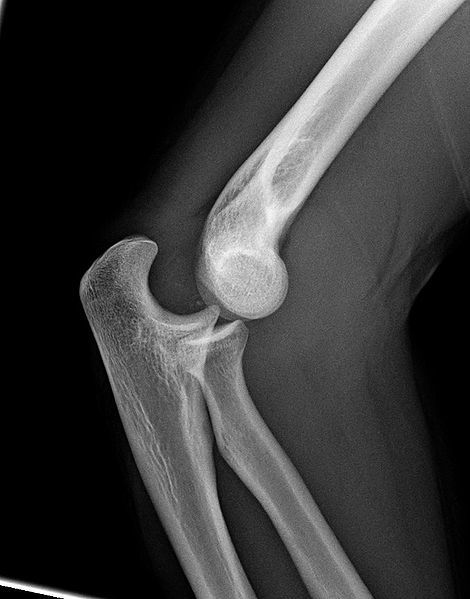

What is shown in the image?

Lateral plain film radiograph of a dislocated right elbow.

For otherwise stable patients, plain film radiographs of the elbow, both AP and lateral, are required initially. Elbow dislocations can be identified from the loss of the radiocapitellar and ulnotrochlea congruence (the anterior humeral line and radiocapitellar line will aid in assessing this).